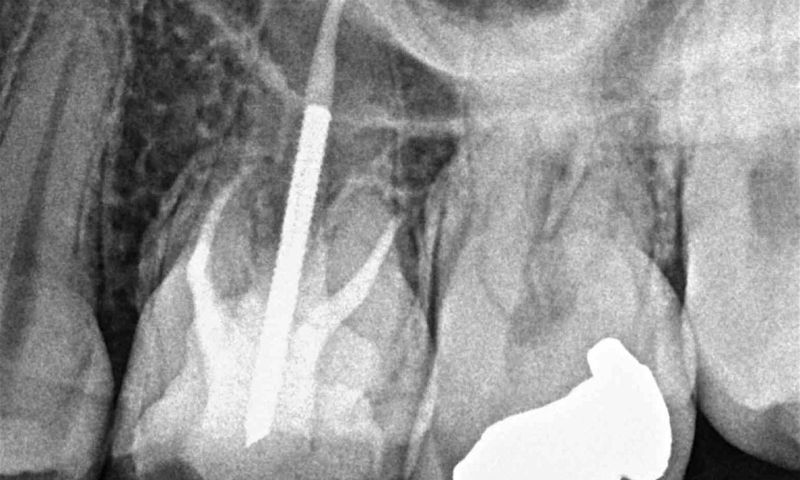

De wortelkanaalbehandeling is de nachtmerrie van iedere tandartspatient. Als je een groot gat in je kies of tand hebt, kan het zijn dat weefsel rondom het wortelkanaal onstoken raakt. De tandarts moet dan de zenuw verwijderen, het wortelkanaal desinfecteren en hermetisch afsluiten, voordat het gat gedicht kan worden met vulling of overkapt kan worden met een kroon. Enerzijds wordt het kanaal hermetisch afgesloten om toekomstige infecties te vermijden, anderzijds omdat de vullingmaterialen toxisch zijn.